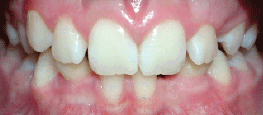

Class II Div I |